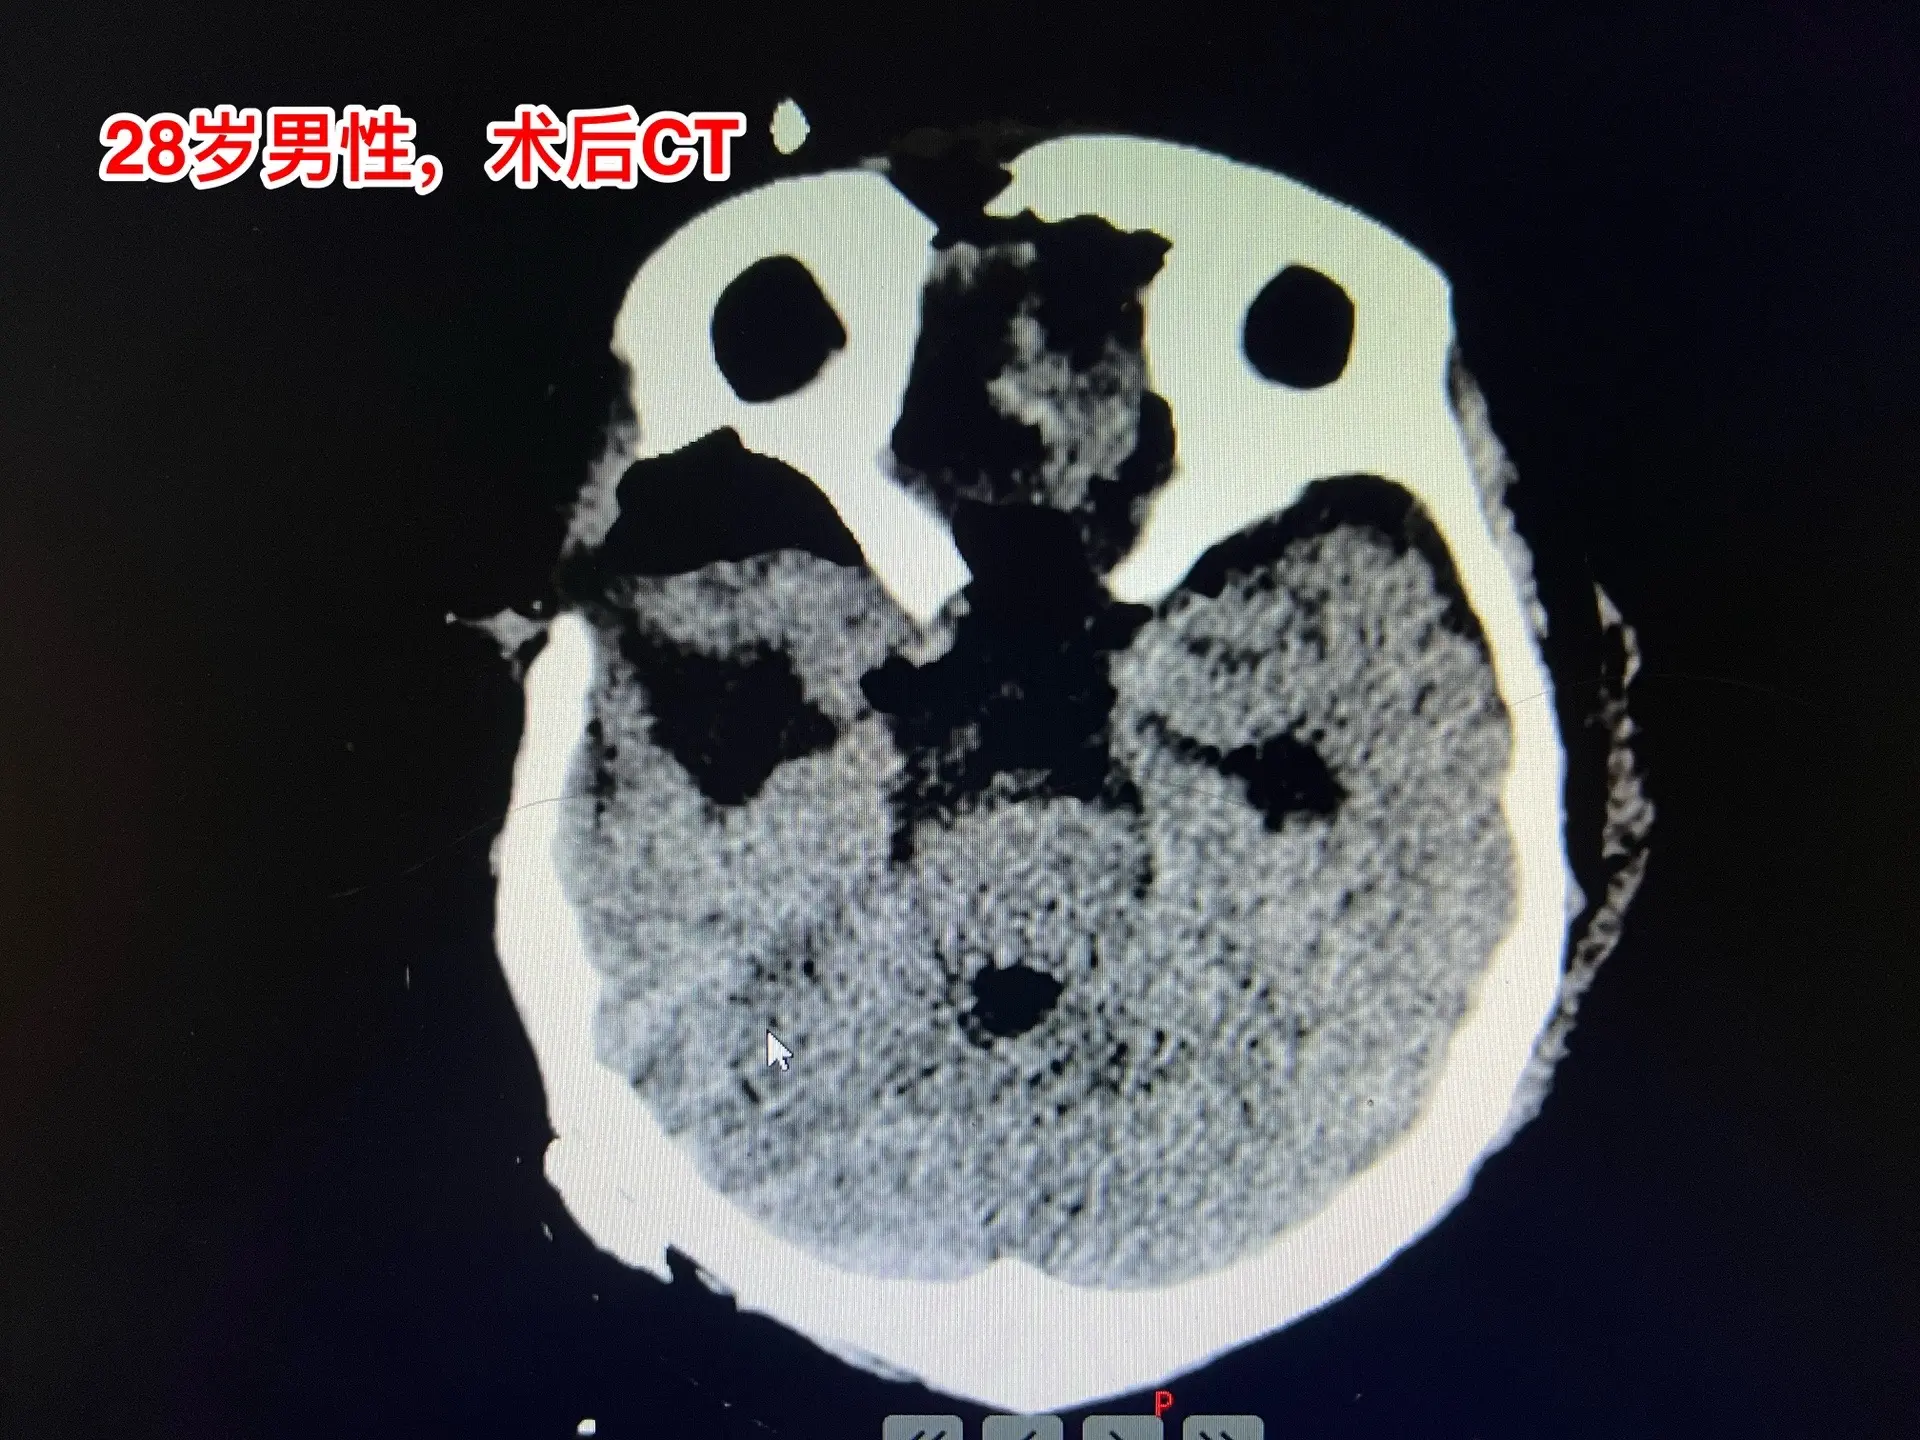

颅咽管瘤四次复发,为挽救视力只能作手术。28岁的四川小伙子,因颅咽管瘤在四川省先后作了四次开颅手术、一次脑室腹腔分流术。2024.6因肿瘤复发还作了一次伽马刀治疗,2024.9复查磁共振显示肿瘤体积在增大。 患者左眼已经失明了,右眼视力也在下降。为了挽救视力,他还是找我想再作一次手术,而且他的心态还是积极乐观的。 11月19日作了手术。原以为这个颅咽管瘤是不可能得到完全切除的,然而手术过程中却发现肿瘤不是一个整体,而是由四块肿瘤组成的,通过各个击破的方式将肿瘤完全切除了。病人右眼的视力也保住了。 希望肿瘤不再复发了!